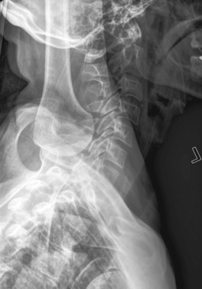

Swimmer’s (Twining Method) C5-T3 Region

• Erect preferred, align C-spine to CR (and centerline of IR).

• Elevate arm and shoulder closest to IR and rotate this shoulder slightly anteriorly or posteriorly.

• Opposite arm down, relax and depress shoulder, with slight opposite rotation (from other shoulder) to separate humeral heads from vertebra. May also be taken in lateral recumbent position with one arm and shoulder down and one up—Pawlow method.